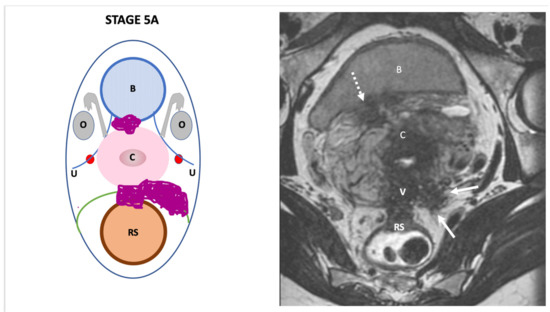

3. The Endo-Stage Mri Classification

| Endo-Stage MRI | Location | Extent | Risk Stratification |

|---|---|---|---|

| Endo-Stage MRI 0 | Superficial endometriosis |

| Low |

| Endometriosis is strictly confined to the ovaries |

| ||

| Endo-Stage MRI I | Endometriosis is strictly confined to the retrocervical area |

| |

| Endo-Stage MRI II | Endometriosis invades beyond the retrocervical area, but not to the pelvic side-wall |

| Endo-Stage MRI III | Endometriosis extends to the pelvic side-wall and/or causes hydronephrosis or non-functioning kidney |

| Intermediate |

| Endo-Stage MRI IV | Endometriosis has involved the bladder or rectosigmoid colon |

| Endo-Stage MRI V | Multiple deep endometrioticlocations |

| High |